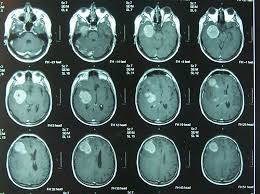

Las células modificadas se inyectaron en el prosencéfalo con una sesión quirúrgica.

Uno de los pacientes murió por una hemorragia

causada por cirugía